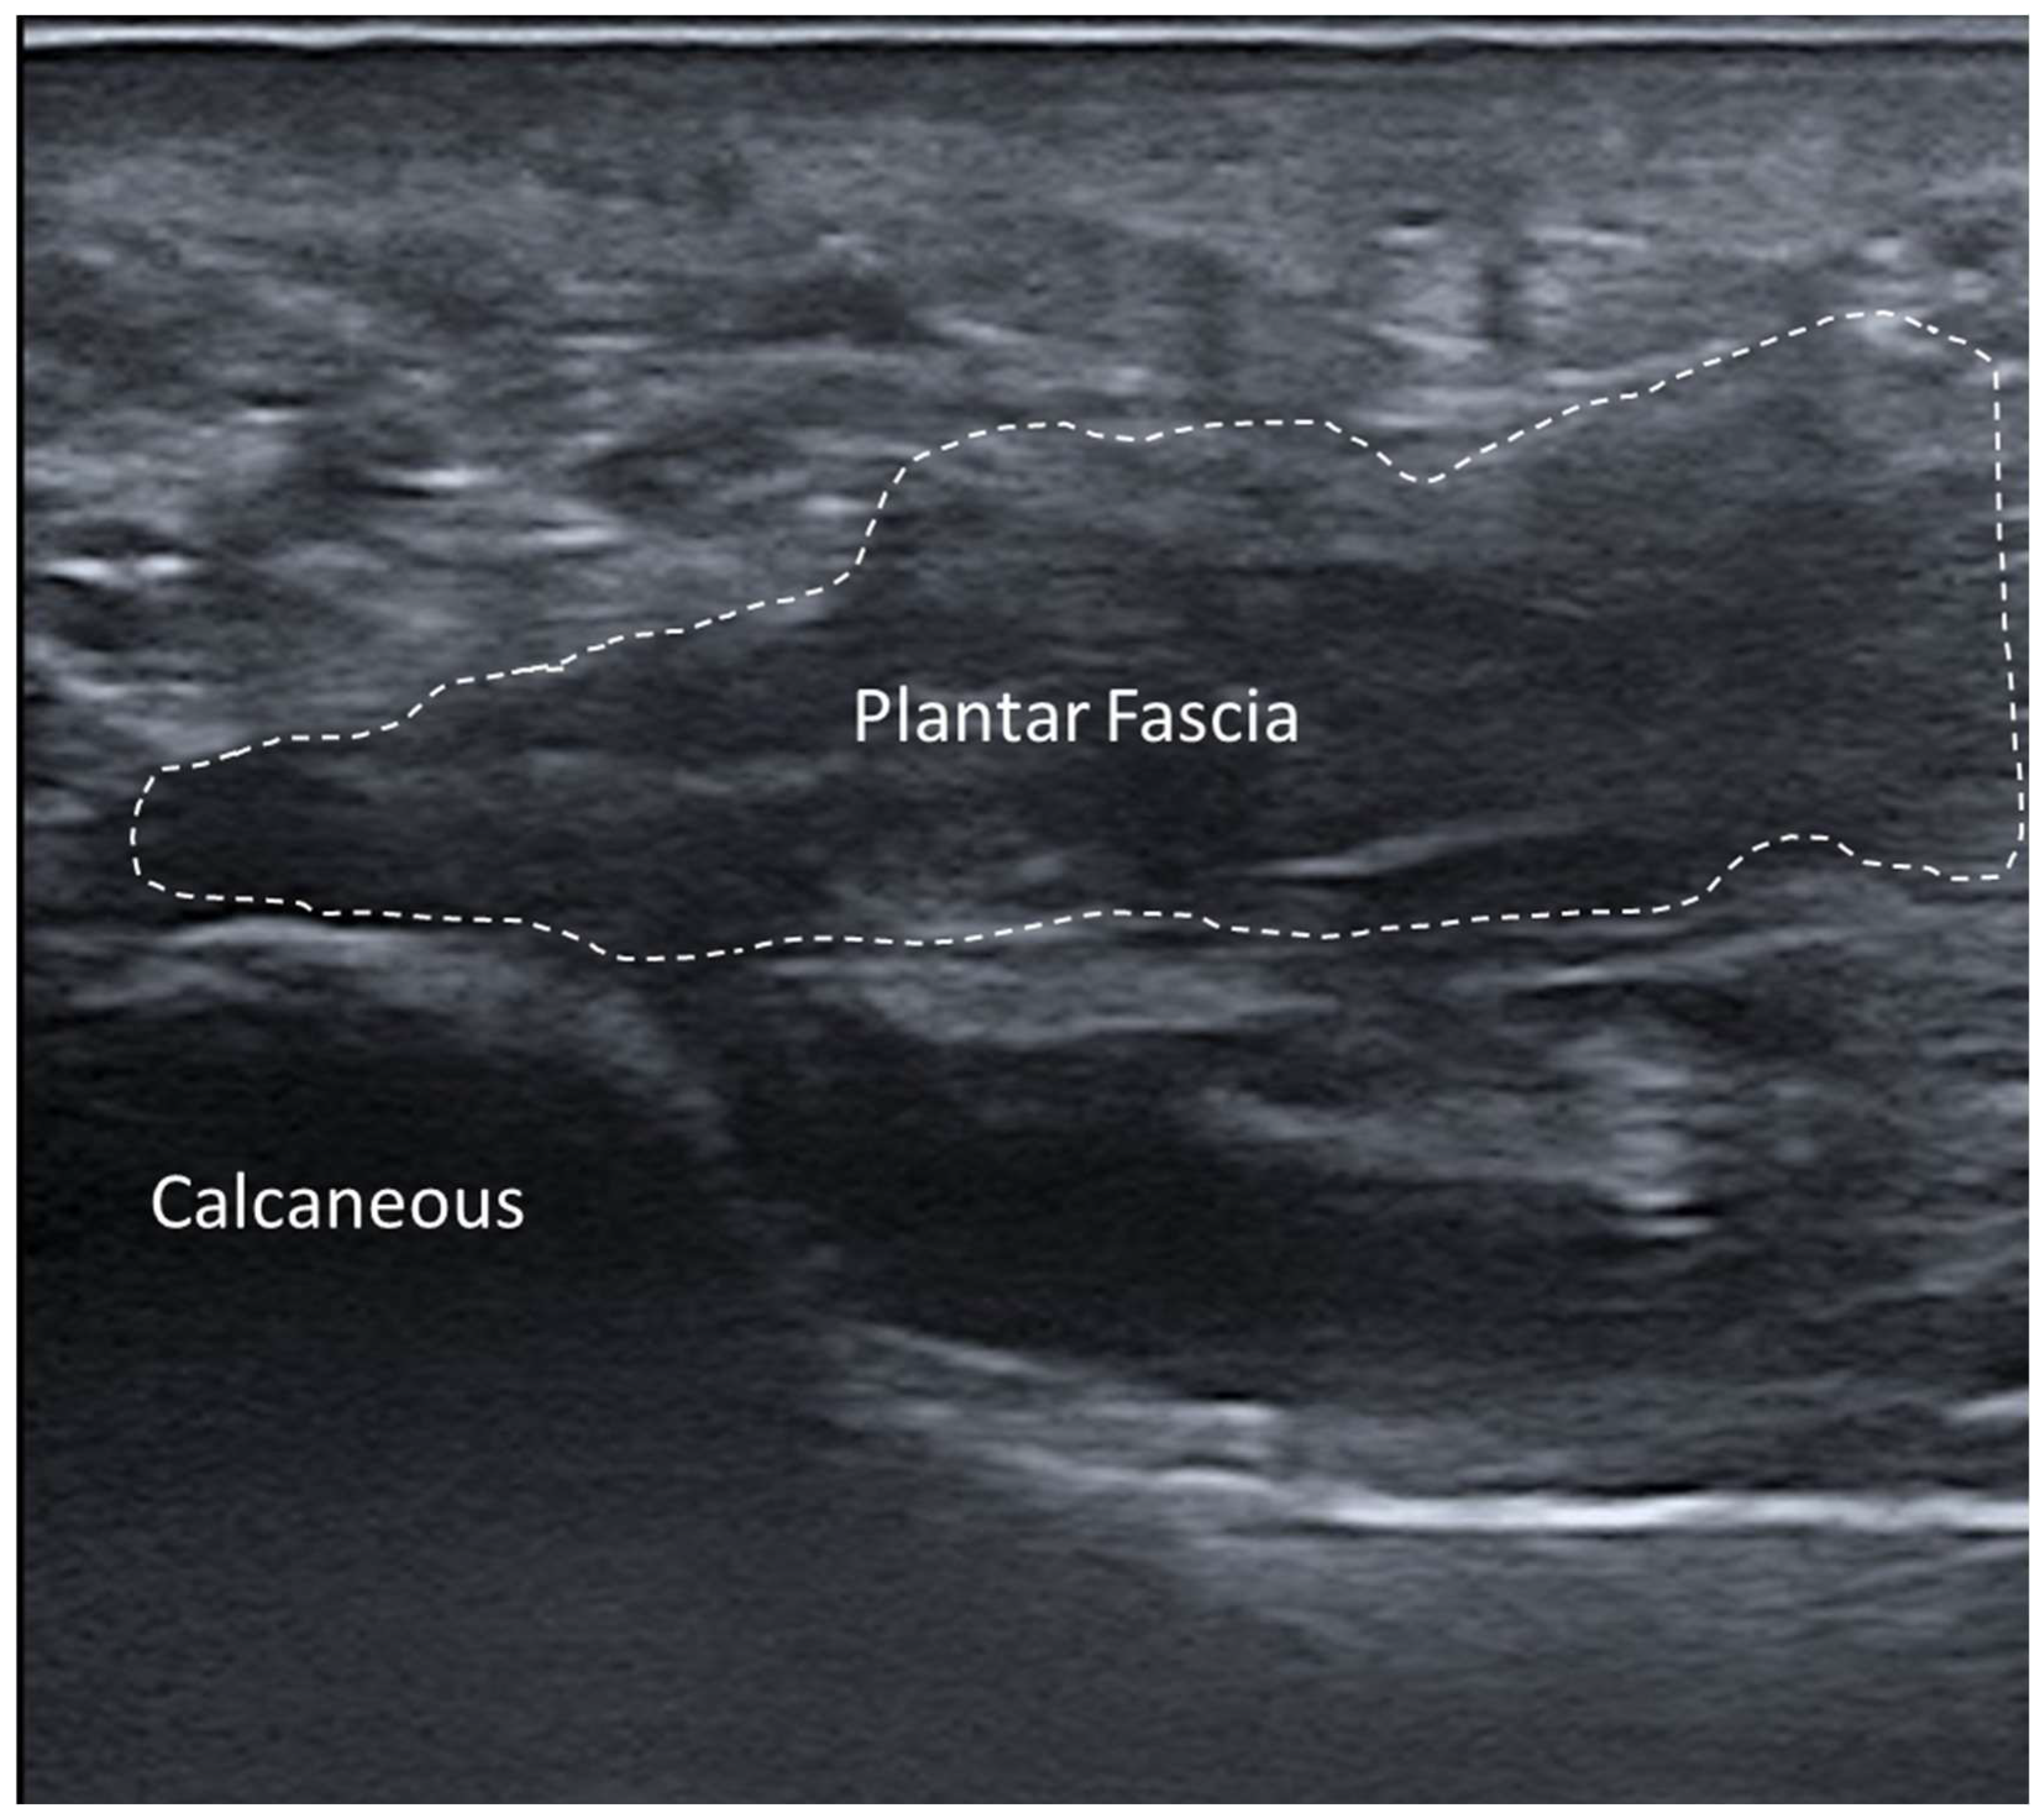

3.5.6. Plantar Fascial Rupture